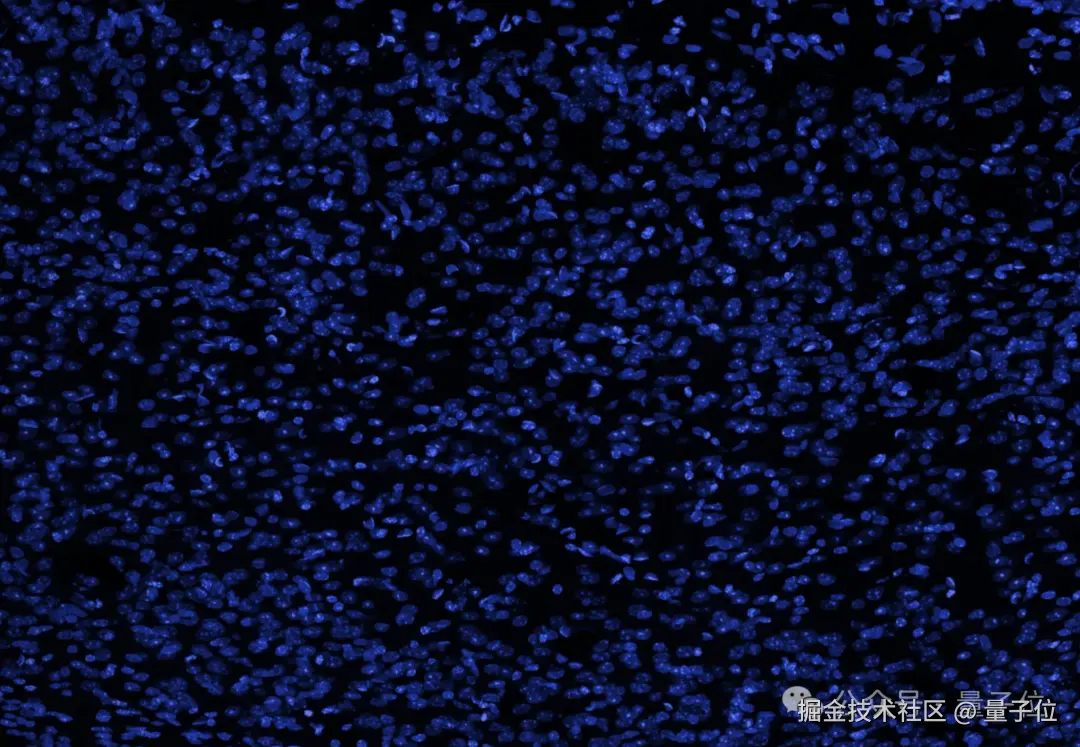

研究团队展示了一张大脑的横截面图像(蓝色表示细胞核),并表示人脑中看似空旷的空间实际上充满了轴突、树突和支持细胞,形成了密集的突触网络。